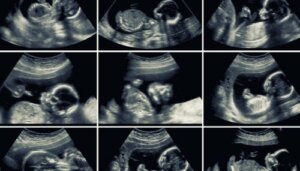

20-Week Ultrasound: Why is it So Important?

The 20-week ultrasound is a routine test that allows a thorough evaluation of the baby’s organs, the mother’s uterus, and the placenta. In addition to the valuable information it offers, it’s carried out at a key moment in pregnancy.

In general, this ultrasound is 2D. However, if the device allows it, some images can be captured in 3D or 4D. The latter shows the baby’s facial features with greater precision and even shows their movements in real-time.

The specialist may combine 2D and 3D images for a more complete analysis of all of the baby’s structures.